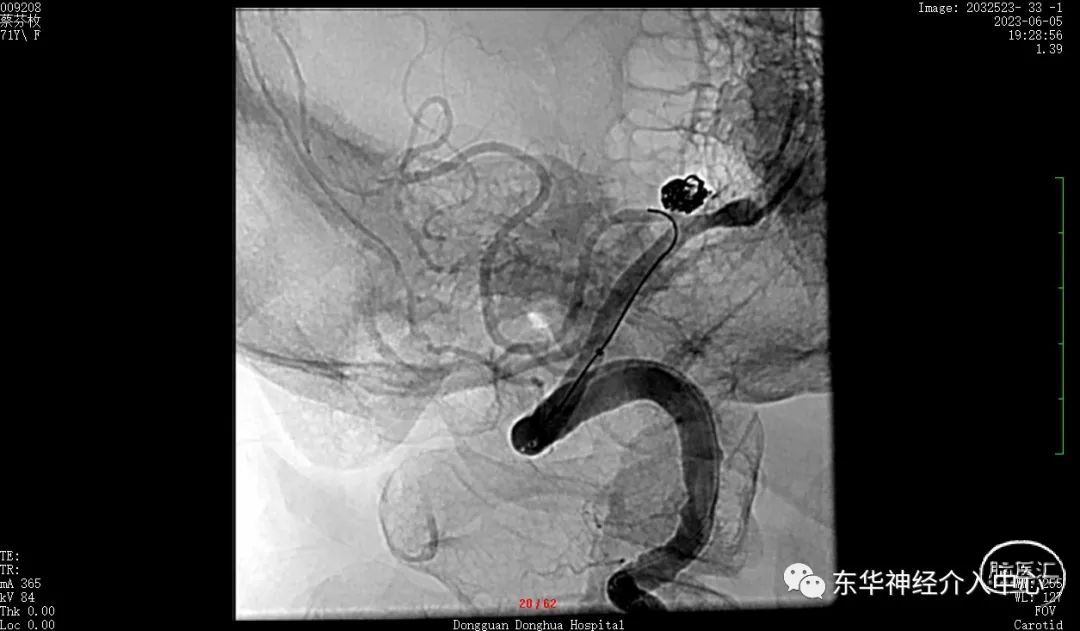

如此信心大增。继续填塞。终于满意的将动脉瘤栓塞,动脉瘤完全不显影。

换一个角度看弹簧圈的形态与动脉瘤的形态基本一致了。

继续换另外一个角度看瘤颈无任何残留。

可见载瘤动脉内微导丝与动脉瘤有间隙,说明动脉瘤成蓝非常满意。

术后3D DSA动态显示栓塞满意、PICA血流无任何影响。